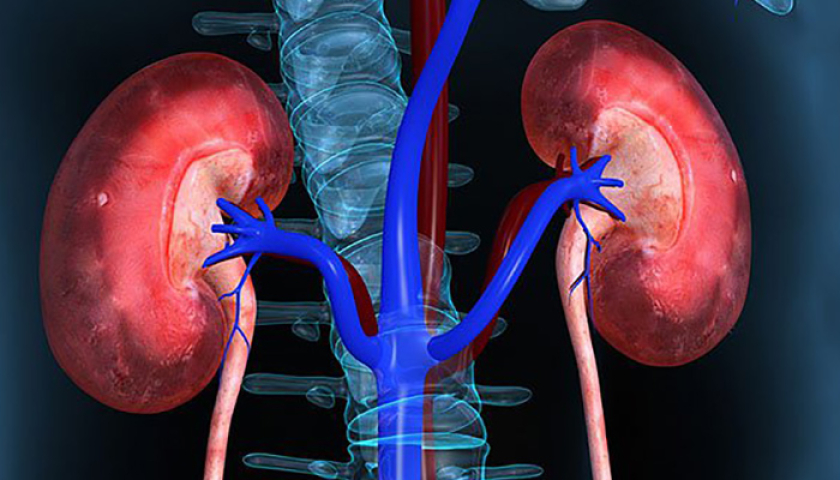

7 thói quen khiến thận ngày một yếu đi

Ăn quá nhiều muối

Muối rất cần thiết nhưng nạp quá nhiều hoặc người có thói quen ăn mặn có thể tăng huyết áp. Huyết áp cao khiến thận phải làm việc nhiều hơn, có khả năng làm hỏng các mạch máu nhỏ bên trong thận. Tổn thương này ngăn thận làm sạch máu đúng cách. Mỗi người nên hạn chế ăn muối, thay vào đó hãy sử dụng các loại thảo mộc hoặc gia vị để tạo hương vị cho món ăn.

Không uống đủ nước

Nước giúp thận đào thải độc tố và chất thải ra khỏi cơ thể. Nếu không uống đủ nước, các chất thải này tích tụ, có thể gây ra sỏi thận hoặc nhiễm trùng. Người trưởng thành cần uống khoảng 2 lít nước mỗi ngày để thận khỏe mạnh, hoạt động tốt.

Lạm dụng thuốc giảm đau

Uống nhiều thuốc giảm đau thường xuyên hoặc số lượng lớn trong một lần có thể gây hại thận. Thuốc giảm đau làm giảm lưu lượng máu đến thận đồng thời gây tổn thương theo thời gian. Người bệnh cần tuân theo chỉ định của bác sĩ về liều lượng, tránh tự ý dùng thuốc.

Tiêu thụ nhiều thực phẩm chế biến

Thực phẩm chế biến như khoai tây chiên, đồ ăn nhẹ đóng gói và các món đóng gói sẵn chứa nhiều muối, đường và chất béo không lành mạnh. Những thành phần này làm tăng nguy cơ cao huyết áp, béo phì và tiểu đường đều tăng áp lực cho thận. Ăn trái cây tươi, rau và nấu ăn tại nhà có lợi cho sức khỏe thận.

Dung nạp quá nhiều protein

Protein rất quan trọng đối với cơ thể song ăn quá nhiều, nhất là từ thực phẩm bổ sung, có thể gây căng thẳng cho thận. Quá trình cơ thể phân hủy protein tạo ra chất thải mà thận phải lọc. Quá nhiều protein có nghĩa là thận phải làm việc nhiều hơn, có khả năng gây tổn thương theo thời gian. Mỗi người nên duy trì các bữa ăn cân bằng với trái cây và rau tươi.

Hút thuốc, uống rượu thường xuyên

Hút thuốc làm giảm lưu lượng máu đến thận, gây tổn thương các mô tại cơ quan này. Rượu gây mất nước, làm tăng huyết áp, cả hai đều tạo áp lực cho thận. Người đồng thời hút thuốc và uống rượu cùng nhau có thể đẩy nhanh quá trình tổn thương thận, phát triển bệnh tật.

Ngủ kém và thường xuyên căng thẳng

Trong thời gian ngủ, thận phục hồi và sửa chữa. Thiếu ngủ hoặc chất lượng giấc ngủ kém có thể gây ra các vấn đề về thận. Căng thẳng cũng ảnh hưởng đến huyết áp cũng như sức khỏe tổng thể, gián tiếp làm tổn thương cơ quan này.

Người trưởng thành nên ngủ 7-8 tiếng mỗi đêm và kiểm soát căng thẳng thông qua thư giãn hoặc tập thể dục.